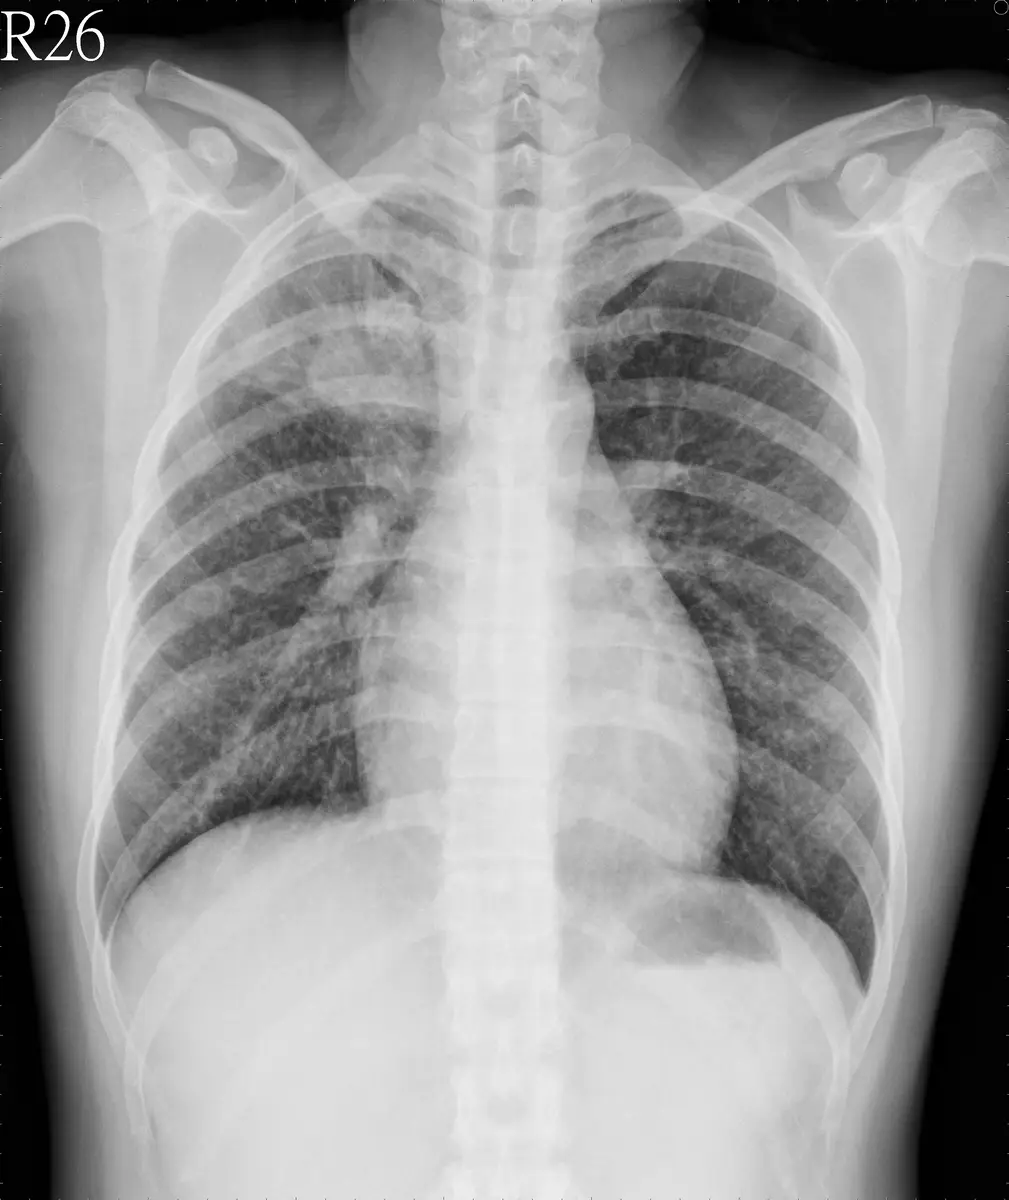

林老太太因為咳嗽兩個月且體重減輕,至門診就醫,胸部 X光如圖所示,最可能的診斷為:

本題提供一張胸部 X 光正面片(PA view):

- 右肺門及右上肺野:可見一明顯的不規則高密度腫塊(large hilar/perihilar mass),位於右側肺門區域,延伸至右上肺野,形成一大片不均勻緻密影。腫塊邊緣不規則,無清楚分界,呈現惡性腫瘤特徵性的分葉或毛刺狀輪廓(lobulated margin)。

- 右側肺門增大:右肺門較左側顯著增大,提示肺門淋巴結腫大(hilar lymphadenopathy)或腫瘤直接侵犯肺門結構。

- 右上肺野透光度降低:右上葉出現大片不透光陰影,可能合併右上葉支氣管阻塞導致的肺萎陷(atelectasis)或腫瘤直接佔據肺實質。

- 左肺及左肺門:相對清晰,無明顯異常。

- 縱膈腔:略有向右側移位的傾向,與右上葉體積縮小(atelectasis)一致。

- 無明顯胸腔積液(pleural effusion):雙側肋